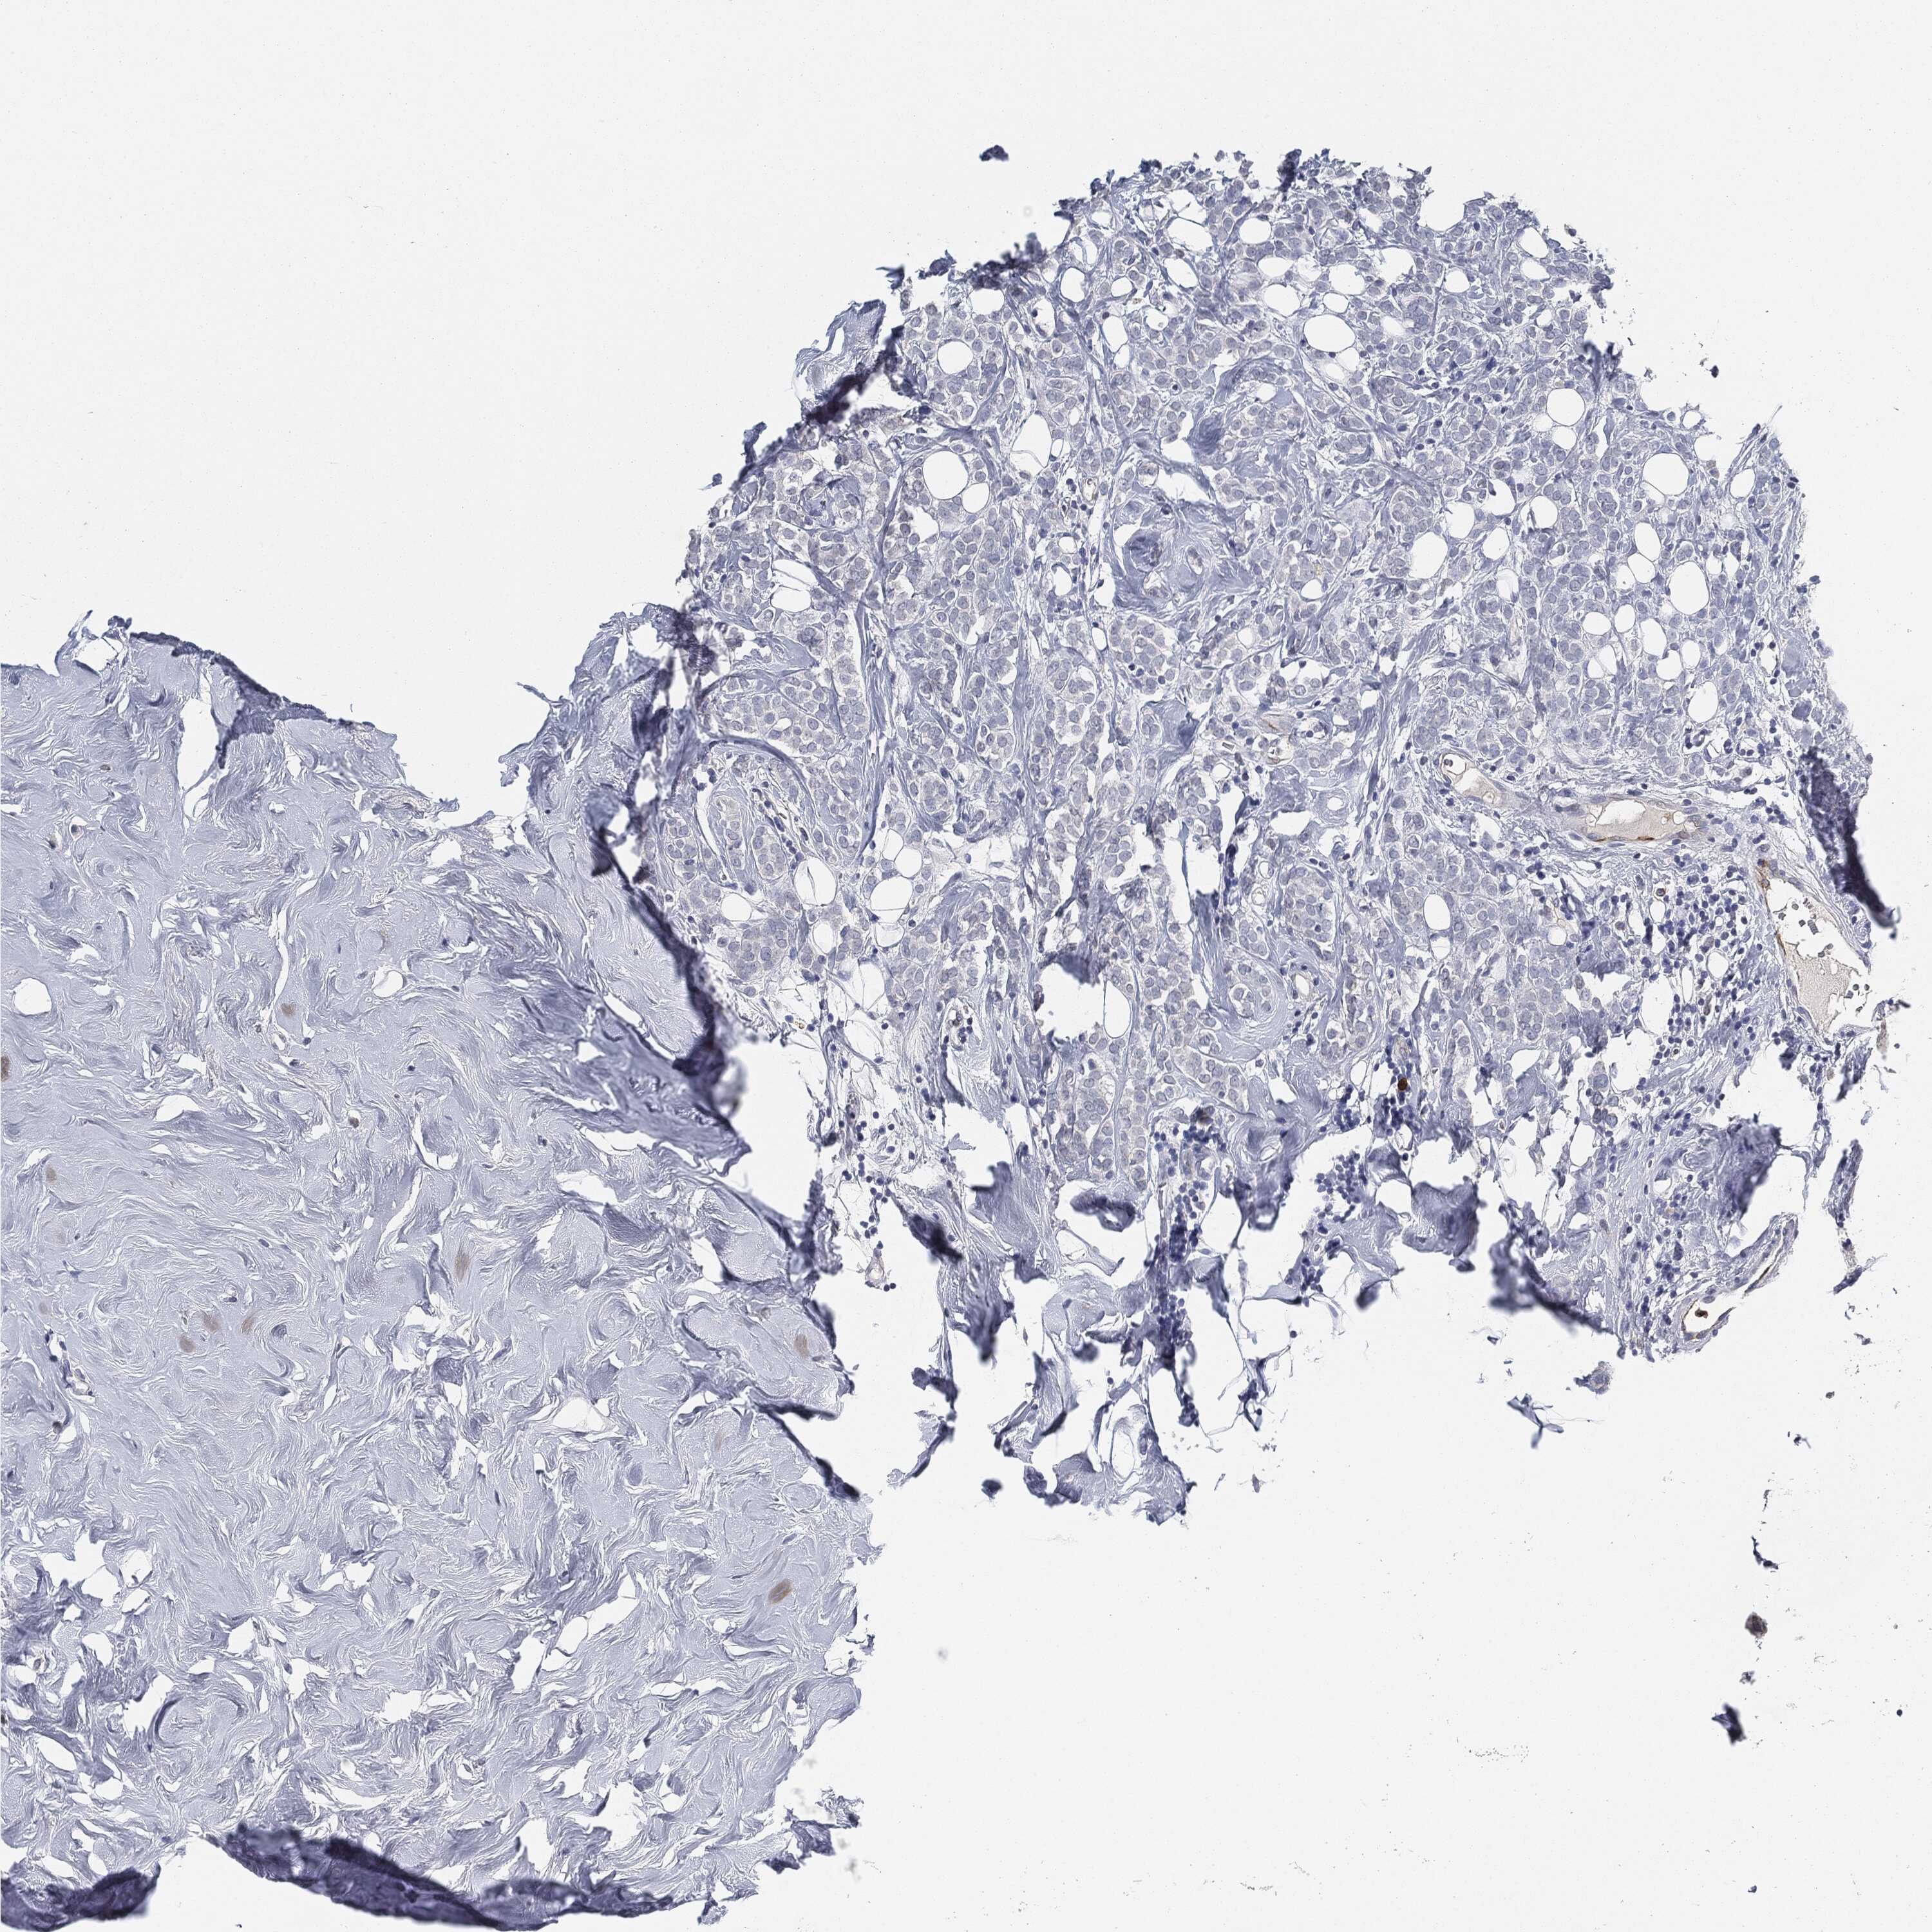

CANCER BREAST CANCER Show tissue menu

BRCA TCGA BRCA VALIDATION PROTEIN EXPRESSION

ANTIBODIES

AND

VALIDATION